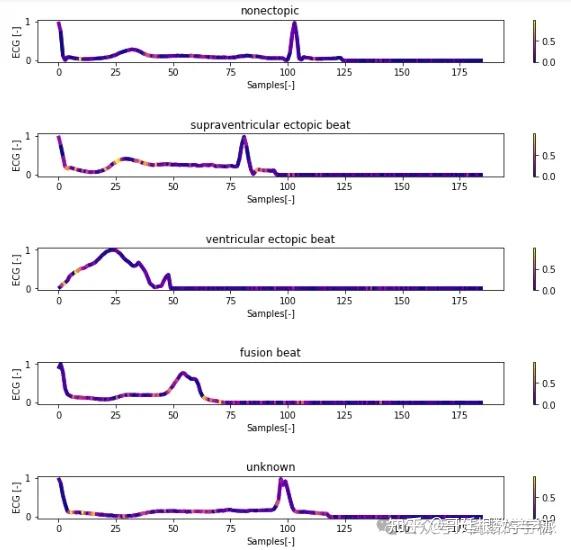

一维神经网络的特征可视化分析-以心电信号为例(Python,Jupyter Notebook)

包括Occlusion sensitivity方法,Saliency map方法,Grad-CAM方法